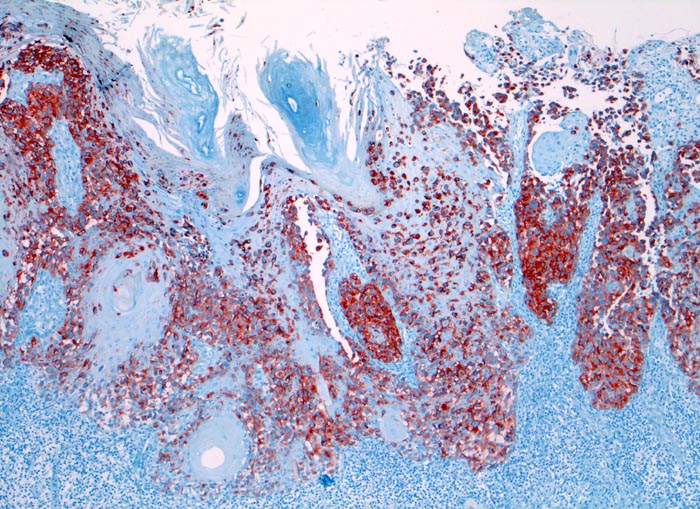

amelanotisches akral lentiginöses Melanom

Haut, Hand palmar, Finger

Die Melanomzellen färben sich an mit dem Melanommarker HMB-45. Dabei wird die Ausdehung der Tumorzellinfiltrate deutlich. An der Oberfläche sind die Zellen diskohäsiv.

Makroskopisch ulzerierte Läsion mit hellbraunem Grund.

Verdacht auf Plattenepithelkarzinom

Histologie

Immunhistochemie

HMB-45